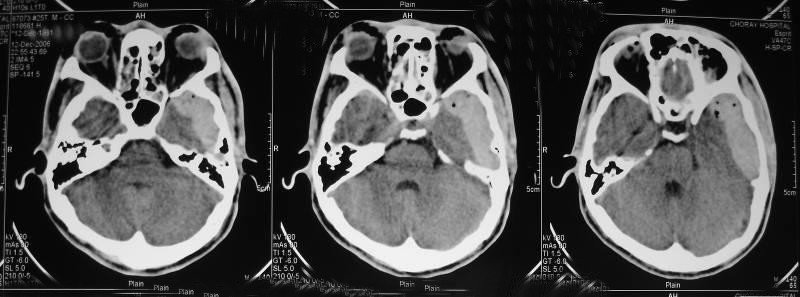

Theo đó, việc chụp cộng hưởng từ nền sọ và xương đá nhằm đánh giá những tổn thương khu trú hay lan tỏa, được tập trung ở vùng nền sọ hoặc xương đá.

Chụp cộng hưởng từ nền sọ và xương đá nhằm đánh giá những tổn thương ở vùng này, vì thế chúng được chỉ định trong trường hợp thăm khám những bệnh lý vùng nền sọ và xương đá, viêm, nhiễm trùng hay tổn thương u. Khi người bệnh có Chấn thương hay những biểu hiện bất thường cần đến ngay cơ sở y tế để được thăm khám và chẩn đoán kịp thời.